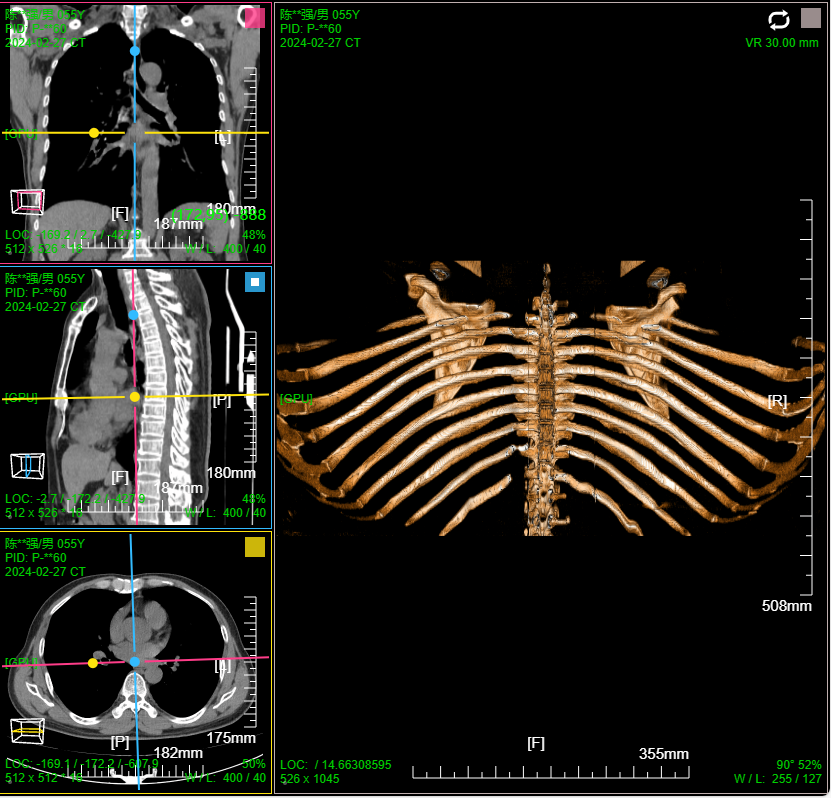

- 支持MPR、CPR、MIP、VR、VE三维图像处理;支持三维裁剪切割 / 一键去床

三维:MPR多平面重建(支持任意旋转)、CPR任意曲线切面重建、MIP最大密度、VR容积重建、VE虚拟内窥;任意三维裁剪、一键去床、一键去头骨、快速旋转、厚切MPR(最大密度/最小密度/均值/VR); 手工/半自动分割,分割目标三维渲染; 肋骨CPR拉伸渲染、牙神经管渲染、血管CPR拉直渲染等

八、三维浏览功能操作和截图

左键双击MPR窗口可在MPR三窗口和1x1窗口间切换;三维渲染窗口左键双击在在1x1视图模式和当前视图模式切换

点击MPR窗口右上角颜色块可AXIS轴位、CORO冠位、SAGI矢位切片切换

鼠标右键点击MPR窗口左下 切片位置指示器 可显隐十字交叉线; 左键点击MPR复位

鼠标左键点击MIP窗口左下 三维旋转状态指示器 可快速旋转到指定面; 右键点击三维旋转复位

厚切支持MIP最大密度 、MINIP最小密度、AVG均值密度、以及VR渲染

改变厚切层厚:1、预设层厚菜单(可配置) 2、拖动滑块快速改变 3、拖动十字交叉线上的层厚虚线

VR容积渲染;鼠标右键默认实时调整当前VR传输函数

支持VR传输函数预设配置; 支持用户自定义配置调整传输函数;

支持自由裁剪切割: 支持自由画笔 和 多边形轮廓选择裁剪区域模式

支持体包围盒裁剪: MPR蓝色mask区域位当前体包围盒设定有效区域

MIP 最大密度投影渲染: 鼠标右键默认实时调窗

肋骨CPR拉伸展开